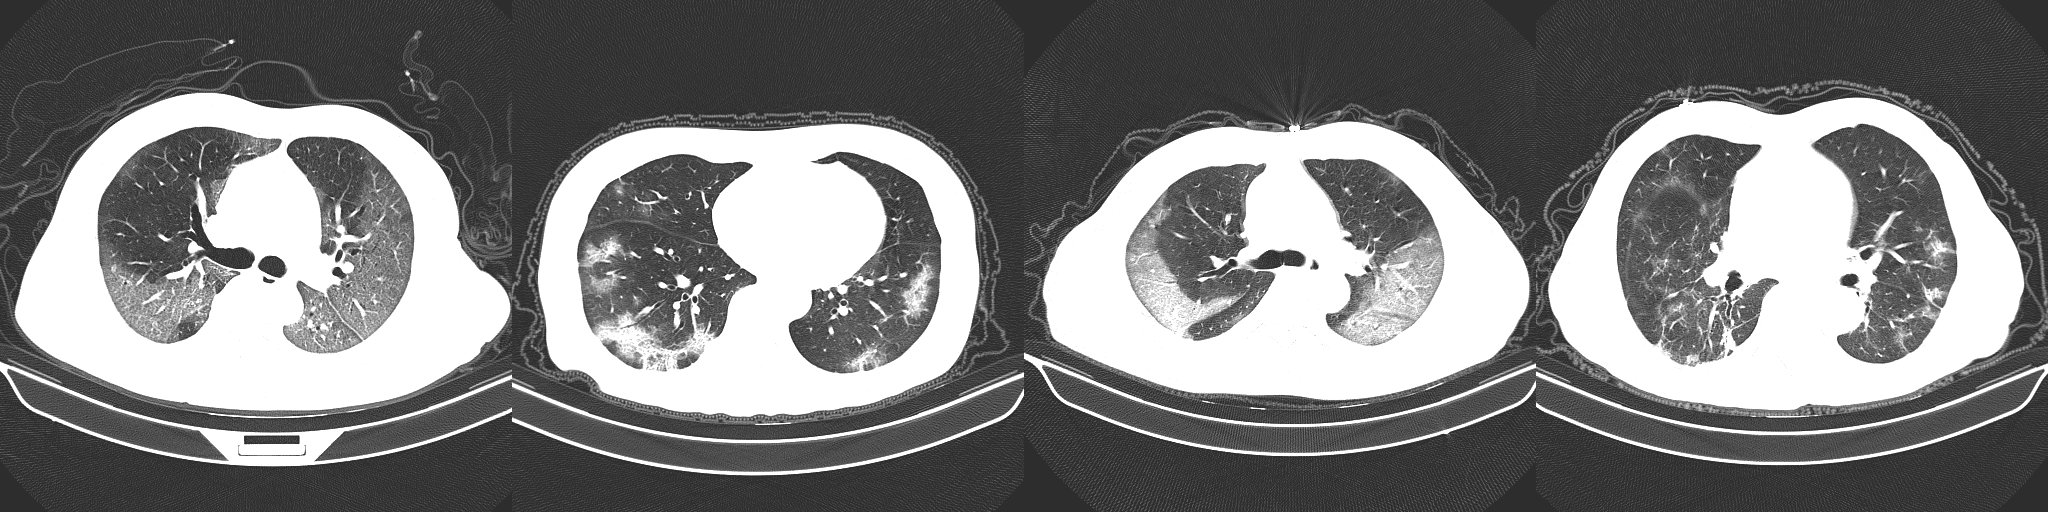

In early studies, it was found that certain abnormalities in chest CT images are indicative of COVID-19 infection, with ground-glass opacities, patchy shadows, crazy-paving pattern, and consolidation being some of the most commonly reported abnormalities, typically with bilateral involvement [11, 12, 13, 14, 5, 4, 6]. Moreover, some studies have found that abnormalities in a patient’s chest CT scan due to COVID-19 infection may be present despite a negative RT-PCR test [5, 4, 6]. However, as illustrated in Figure 1, these imaging abnormalities may not be specific to COVID-19 infection, and the visual differences between COVID-19-related abnormalities and other abnormalities can be quite subtle. As a result, the performance of radiologists in distinguishing COVID-19-related abnormalities from abnormalities of other etiology may vary considerably [15, 16]. For radiologists, visual analysis of CT scans is also a time-consuming manual task, particularly when patient volume is high or in large studies.

Figure 1: Example chest CT abnormalities in (a) a patient with COVID-19 pneumonia, and (b) a patient with non-COVID-19 pneumonia. It can be observed that visual difference in abnormalities between COVID-19 pneumonia and non-COVID-19 penumonia can be quite subtle.